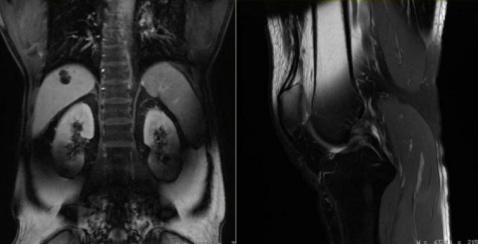

1. 磁场干扰:金属物会扭曲磁场,就像在平静的湖面扔石头,导致图像出现漩涡状伪影,重要病灶可能被完全掩盖。

2. 信号黑洞:金属会吸收无线电波,在图像上形成黑色空洞(就像照片被泼了墨水),周围组织细节全部消失。

3. 位置偏移:体内金属(如钢钉、假牙)可能轻微移位,导致图像扭曲变形,医生可能误判骨折愈合情况。